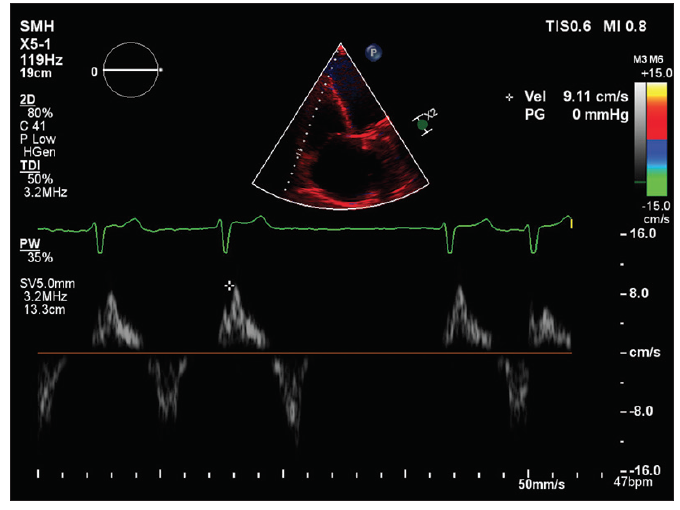

Dr. Hahn: Multiple modalities can be used to assess RV size and function (CT, cardiovascular magnetic resonance, echocardiography), with recent studies suggesting that RV strain (either by echocardiography or cardiovascular magnetic resonance) can possibly predict outcomes. In truth, we don’t know the best way to assess RV plasticity and its ability to recover. Evaluation of RV–pulmonary artery coupling may also play a role. On echocardiography, tricuspid annular plane systolic excursion, fractional area change, and tissue Doppler S´ are the easiest to measure; however, free wall strain (or global longitudinal strain including the septum) may be superior to these methods.

Dr. Taramasso: TEE with assessment of RV strain is probably the most reliable way, with MRI used in selected cases. However, the visual impression from the TEE images still plays an important role, especially when the numbers indicate an apparently normal RV function. In the presence of RV dysfunction, any intervention may be futile or even dangerous due to the acute postprocedural risk of afterload mismatch. Severe RV dysfunction normally represents a contraindication to intervention.